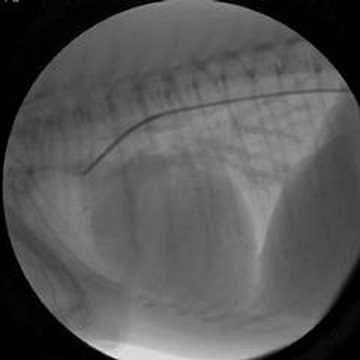

Persistência do ducto arterioso

Fluoroscopia mostrando a persistência do ducto arterioso de um cão.